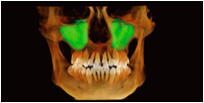

Visualização 3D do Seio Maxilar

Gera automaticamente a estrutura 3D do seio maxilar.

Permite uma observação clara da morfologia do seio e ajuda a avaliar os riscos cirúrgicos em implantes maxilares.

Auxilia na avaliação do volume de enxerto em elevação do seio maxilar